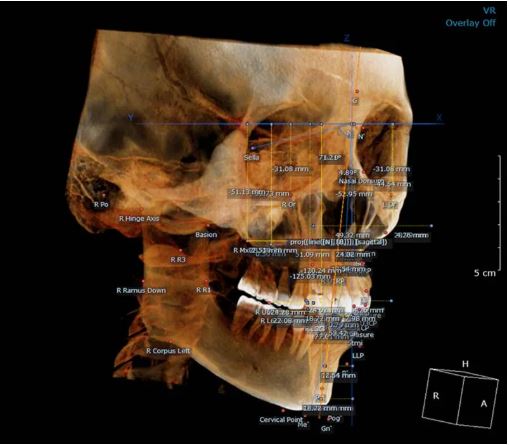

• Optional Cephalometric X-ray

An attachable cephalometric arm enables accurate scan-type cephalometric imaging, essential for orthodontic treatment planning and airway structure analysis.

An attachable cephalometric arm enables precise scan-type cephalometric imaging, making it a powerful tool for orthodontic evaluations and treatment planning.